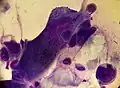

![]() A positive Tzanck test, showing three multinucleated giant cells ("Tzanck cells") in center. | |

| Herpetic infections | Acantholytic cells, multinucleated giant cells and eosinophilic inclusion bodies | 53.1 - 86% sensitive and 100% specific | ||